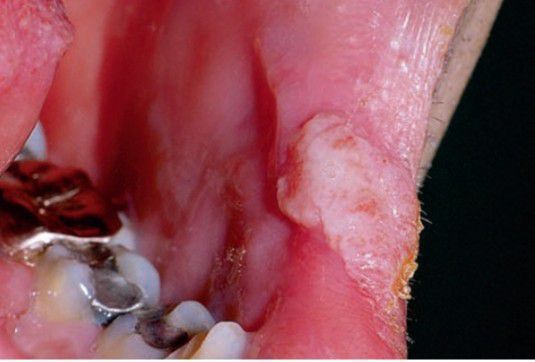

Condyloma latum

Clinically similar to papillary hyperplasia; part of secondary syphilis.